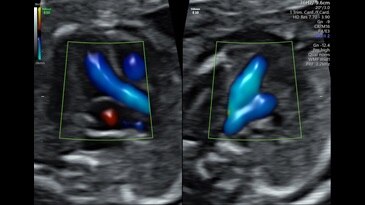

15-week fetal circulatory system with eSTIC and HD-Flow™

3VV and LVOT with Radiantflow™ in Dual Display